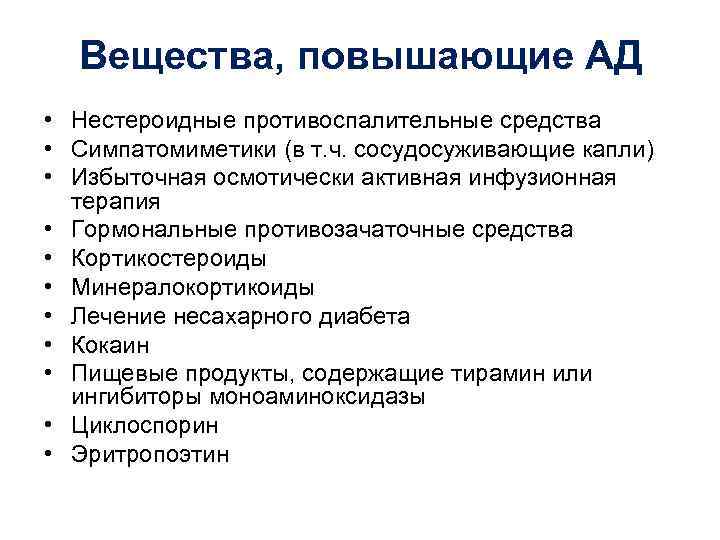

Вещества, повышающие АД • Нестероидные противоспалительные средства • Симпатомиметики (в т. ч. сосудосуживающие капли) • Избыточная осмотически активная инфузионная терапия • Гормональные противозачаточные средства • Кортикостероиды • Минералокортикоиды • Лечение несахарного диабета • Кокаин • Пищевые продукты, содержащие тирамин или ингибиторы моноаминоксидазы • Циклоспорин • Эритропоэтин

Вещества, повышающие АД • Нестероидные противоспалительные средства • Симпатомиметики (в т. ч. сосудосуживающие капли) • Избыточная осмотически активная инфузионная терапия • Гормональные противозачаточные средства • Кортикостероиды • Минералокортикоиды • Лечение несахарного диабета • Кокаин • Пищевые продукты, содержащие тирамин или ингибиторы моноаминоксидазы • Циклоспорин • Эритропоэтин